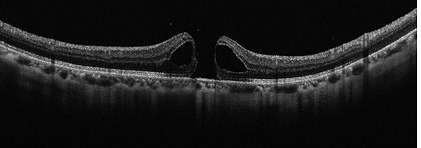

黄斑円孔

中心部分が見えづらくなる(中心暗点)や物がゆがんで見えるなどの症状が生じるとされています。

治療としては、現在のところ、点眼薬や内服薬による治療法はなく、手術(硝子体手術)が唯一の治療法となっています。当院では、必要に応じて連携する医療機関をご紹介しております。